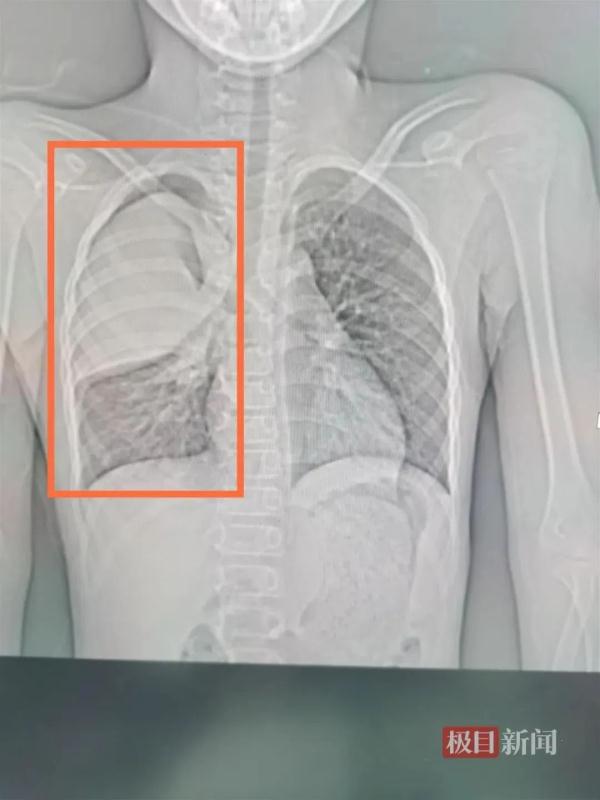

△右上肺三分之二出现白肺。

武汉市肺科医院呼吸二病区副主任杨澄清说,CT检查发现,孩子的右肺“大片状实变”,也就是常说的“白肺”。通过相关检查,小阳的支原体抗体呈阳性,肺炎支原体核酸阳性,随即确诊为肺炎支原体肺炎。